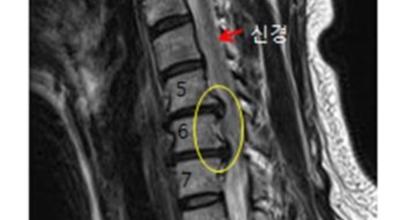

목디스크 증상이 나타날때 빨리 발견하여 비수술 치료를 받고 꾸준히 관리하는 것이 베스트이죠. 목디스크 환자 중 수술을 진행하는 환자는 2% 미만으로 현저히 적다고 해요. 수술을 진행하는 경우는 감각이 느껴지지 않는 마미증후군이나, 한쪽 다리가 눈에 띌 정도로 야윈 경우에만 진행하므로 올바른 자세 교정만으로도 충분히 호전될 수 있는 질병이죠. 목에 연관된 검사는 MRI나 CT를 이용해요. 그러나 전자의 경우 비용이 굉장히 비싸기 때문에 디스크 증세가 확실하다고 생각될 경우에만 선택적으로 하고 의무적으로 하는 건 아니니까 비용에 대해선 부담을 가지지 마시길 바래요.

목디스크 증상으로 인해 3개월 이상 약물이나 물리치료를 해도 효과가 없을 경우 수술을 고려해야 해요. 통증이 심해서 일상생활에 지장이 있거나, 신경증상이 악화되고 근력도 함께 줄어들 때와 큰 디스크가 탈출해 중추신경인 척수를 압박해 척수증이 발생하는 경우에도 수술을 고려할 수 있어요.